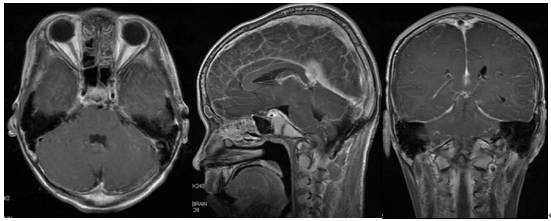

辅助检查:MRI平扫加增强显示第四脑室内可见不规则肿块影,T1WI呈高低混杂信号,T2WI呈混杂低信号,增强扫描可见不均匀强化,大小约36x25.7x51.1mm,脑桥延髓后部及小脑蚓部受压。诊断“第四脑室肿块,室管膜瘤?”(图1)。

图1. MRI检查:第四脑室内可见不规则肿块影,T1WI呈高低混杂信号,T2WI呈混杂低信号,增强扫描可见不均匀强化,脑桥延髓后部及小脑蚓部受压。